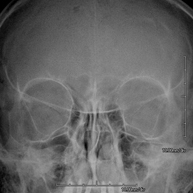

- Orbit X-ray

This technique uses X-ray rendered imaging for examining the orbits. Indicated for: ocular foreign body, trauma, infections.